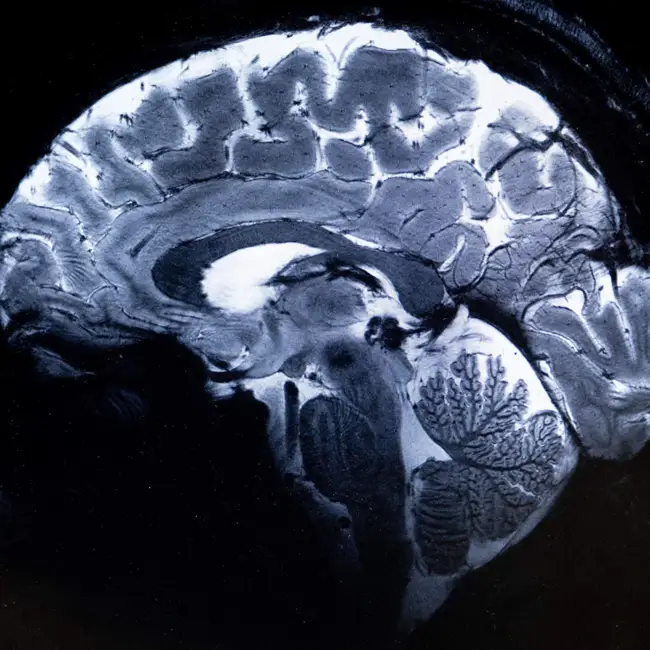

There’s this idea that something happens in the human brain when we turn 25. Suddenly, we can rent a car without fees. Make rational decisions. We may even regret some of our past… indiscretions. All because we’re developed…right? Well, a recent paper in the journal Nature suggests that may not be the case. Neuroscientists found four distinct turning points in brain development across the human lifespan – and that the brain may be in its “adolescent” phase until about the age of 32.  Interested in more of the science inside your brain? Email us your question at shortwave@npr.org. Listen to every episode of Short Wave sponsor-free and support our work at NPR by signing up for Short Wave+ at plus.npr.org/shortwave. This episode was produced by Rachel Carlson. It was edited by Rebecca Ramirez. Tyler Jones checked the facts. The audio engineer was Kwesi Lee. Learn more about sponsor message choices: podcastchoices.com/adchoices NPR Privacy Policy

There’s this idea that something happens in the human brain when we turn 25. Suddenly, we can rent a car without fees. Make rational decisions. We may even regret some of our past… indiscretions. All...